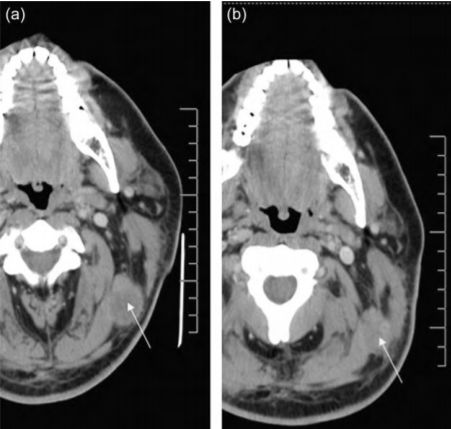

NK细胞的工作机制是,如果细胞表达的MHC-I类分子正常,KIR(抑制性杀伤细吧免疫球蛋白样受体)表达正常,NK细胞就不工作。相反,如果MHC-I 类分子下调,KIR表达降低,NK细胞就容易被激活,一些被激活的NK细胞受体,如NKG2D、NKp30、NKp46和NKp44,可以识别靶细胞上表达的应激诱导配体,从而为NK细胞杀伤靶细胞提供积极的信号,开启杀伤模式。所以,当具有表达MHC-I类分子较少或缺失的细胞,NK细胞就被激活,这就是“抗癌第一道防线”的真面目。NK细胞具有广谱的抗肿瘤作用,不显示肿瘤杀伤的特异性和MHC限制性,在机体其它免疫细胞(如T、B细胞)功能低下时,NK细胞的作用尤为重要!NK细胞对几乎所有常见的癌细胞类型都有杀伤作用,包括肺癌、乳腺癌、肝癌、淋巴癌、食道癌等。而NK细胞的杀敌方式也不拘泥于一种,它的抗癌机制非常多样。除了被激活释放细胞受体来对抗外敌,NK细胞还可以通过释放穿孔素和颗粒酶或通过死亡受体直接杀死癌细胞;同时还可以通过分泌细胞因子和趋化因子,调节先天性和获得性免疫细胞间接杀死病变细胞;另外,NK细胞还能够与肿瘤细胞表面的抗体相结合,发挥细胞毒性作用杀死靶细胞。这些都是NK细胞抗癌的作用机制,由于NK细胞抗癌的广谱性,近年来关于NK细胞用于治疗各种癌症的研究也越来越多。在最新的研究中,NK细胞疗法已经被广泛应用于各种癌症治疗,包括:血液系统肿瘤、神经母细胞瘤、卵巢肿瘤、横纹肌肉瘤、乳腺癌、胃癌等。并在这些研究中取得不错治疗效果。2008年,美国拉什大学医学中心的研究人员将外源扩增的NK异体细胞注入到黑色素瘤患者体内,结果发现,注入NK细胞后,该患者左上颈部肿瘤的体积明显降低(从3.15 cm×2.54 cm减小至2.46 cm× 1.76 cm)。同时,该研究也为外源扩增的NK异体细胞是否可以大规模应用于治疗黑色素瘤提供了一定的理论依据。2013年,另一项研究在对3625名癌症患者长达11年的随访中,确定了NK细胞的活性越好和更好的癌症治疗效果以及更低的癌症复发风险相关。不论是在胃癌、神经母细胞瘤还是结直肠癌患者群体中,都有相同观察结果。